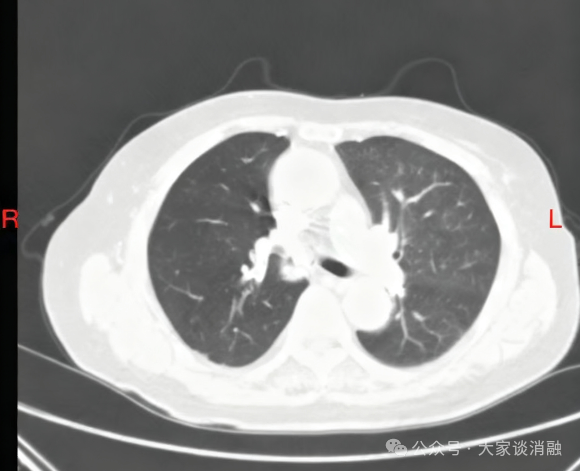

夏奶奶近两年来一直被间断的胸闷、气短、咳嗽、咳痰困扰。半月前,她的病情急剧加重,出现了痰中带血的症状,家人紧急送至东院区。呼吸与危重症医学科阎杰副主任医师接诊后,立即为夏奶奶进行胸部增强CT检查。结果提示“右肺门增大,右肺主支气管内结节状软组织密度灶,右肺下叶不张”,高度怀疑恶性肿瘤。

*患者CT检查